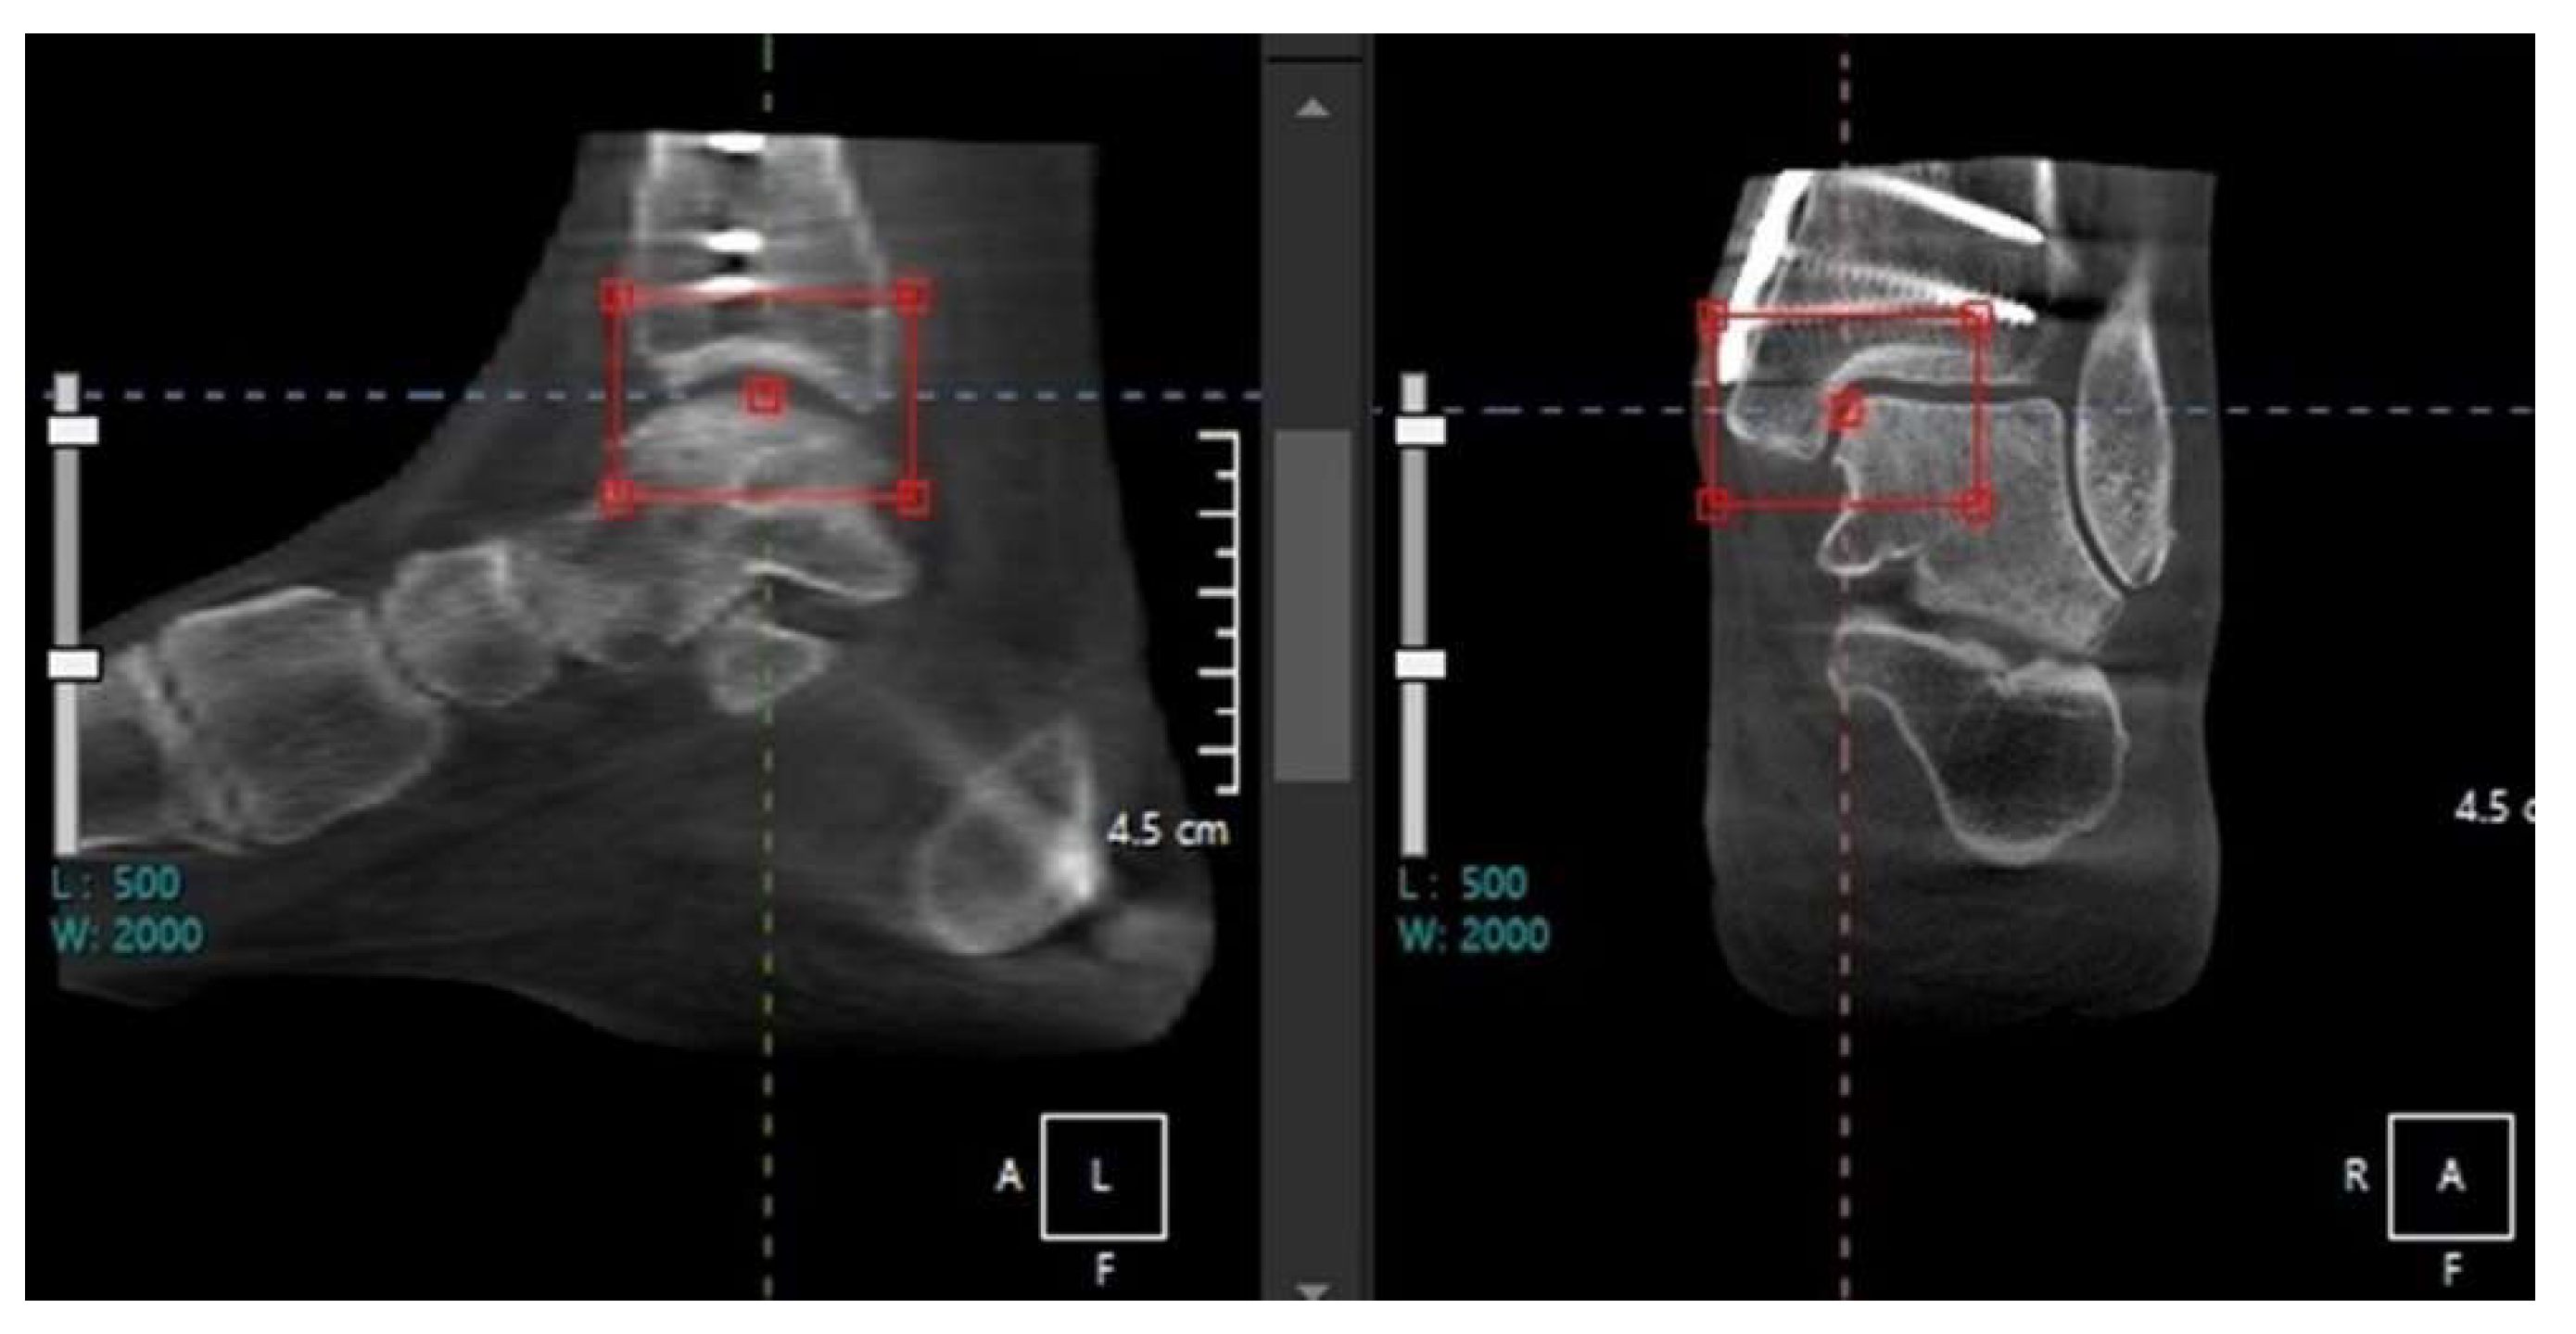

The hindfoot alignment and compensation of the subtalar joint should also be taken into consideration when making therapeutic strategies for ankle OA. Because the measurements in hindfoot alignment view are known to be sensitive to changes in x-ray beam projection angle, WBCT is particularly useful to evaluate the hindfoot alignment [13,14]. Krähenbühl et al evaluated the subtalar joint orientation using coronal WBCT images and concluded that the subtalar joint was more varus oriented in varus ankle OA while more valgus oriented in valgus ankle OA (Figure 3) [15]. They also studied the degree of inframalleolar compensation against supramalleolar abnormalities with WBCT, stating that subtalar joint compensation occurred in varus ankle OA whereas it did not happen in valgus ankle OA. Similarly, Kang et al focused on subtalar compensation in advanced varus ankle arthritis and found that ankle OA with talar tilt angle greater than 9.5 degrees is significantly prone to a non-compensated heel [16]. Likewise, WBCT is actively being used to explain the hindfoot alignment and subtalar joint characteristics in ankle OA.

Figure 3. Weight-bearing plain radiographs of patients with various types of tibiotalar alignment (A-1, B-1, C-1) and corresponding subtalar joint orientation in WBCT (A-2, B-2, C2). The subtalar vertical angle (SVA) was defined as the inclination of the line connecting the medial and lateral aspects of the talus with a vertical line, which is perpendicular to the ground.